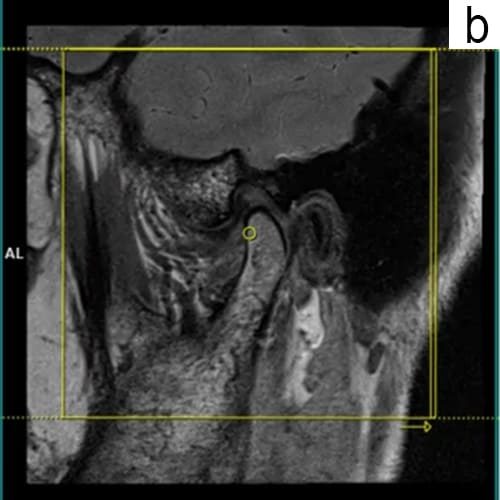

a. Temporomandibular disorder (TMD) is diagnosed primarily through a detailed medical history and physical examination, focusing on symptoms such as jaw pain and clicking sounds.

b. Clinicians may use the Diagnostic Criteria for Temporomandibular Disorders (DC/TMD), which includes both clinical assessments and imaging techniques like MRI or X-rays to evaluate joint function and rule out other conditions.

c. Additional diagnostic tools may include ultrasound and electromyography to assess muscle function and joint health.